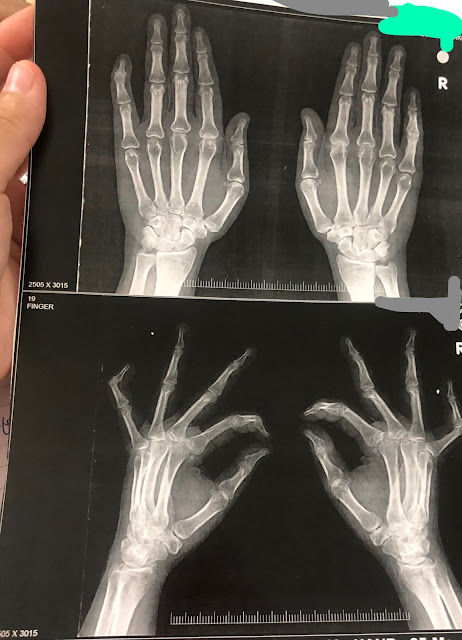

A 40 year old woman was apparently asymptomatic 7 years back after which she started experiencing multiple joint pains. She reported that she first experienced right proximal interphalangeal joint pain 7 years back while she was working on the sewing machine. After 2 weeks she started to experience left proximal interphalangeal joint pain. Over the last 7 years, she started experiencing multiple joint pains - bilatered meta-carpophalangeal joint, bilateral elbow joint, bilateral wrist joint, cervival joint, bilateral knee joint, bilateral ankle joint pains. She reported early morning stiffness lasting for more than an hour which would be relieved on physical activity. She would experience these pains intermittently and would often be accompanied by swelling of the joint and would be relieved on taking pain medications. She reported that she developed bilateral little finger deformity 1 year back.

Boutenniere' or button hole deformity of the right little finger &

Swan neck deformity of the left little finger: